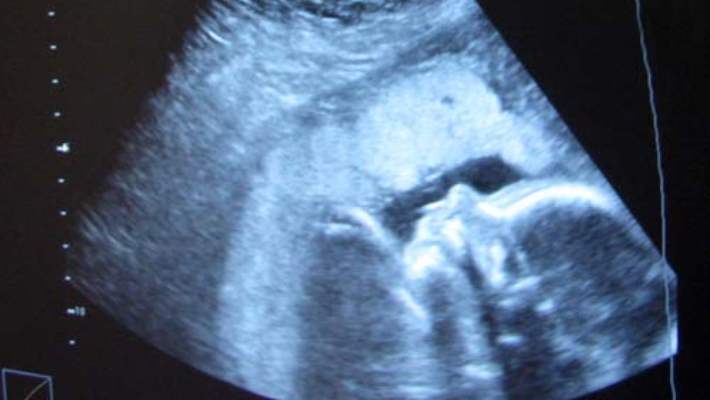

Dış gebelik, gebeliğin rahim içinden başka bir yere yerleşip orada büyümeye devam etmesidir. Bunun nasıl gerçekleştiği meselesine gelince; aslında bütün gebelikler dış gebelik olarak başlar. Döllenme ve gebelik tüpte oluşur, 10-12 gün süren bir yolculuktan sonra rahim içine gelir yerleşir ve burada büyümeye devam eder. Herhangi bir şekilde bu yolculuğu engelleyen bir darlık, tıkanıklık, yapışıklık ve benzeri bir nedenle, gebelik ürünü rahim içine ulaşmadan herhangi bir yerde üremeye başlar ve devam ederse, dış gebelik denilen tablo oluşur.